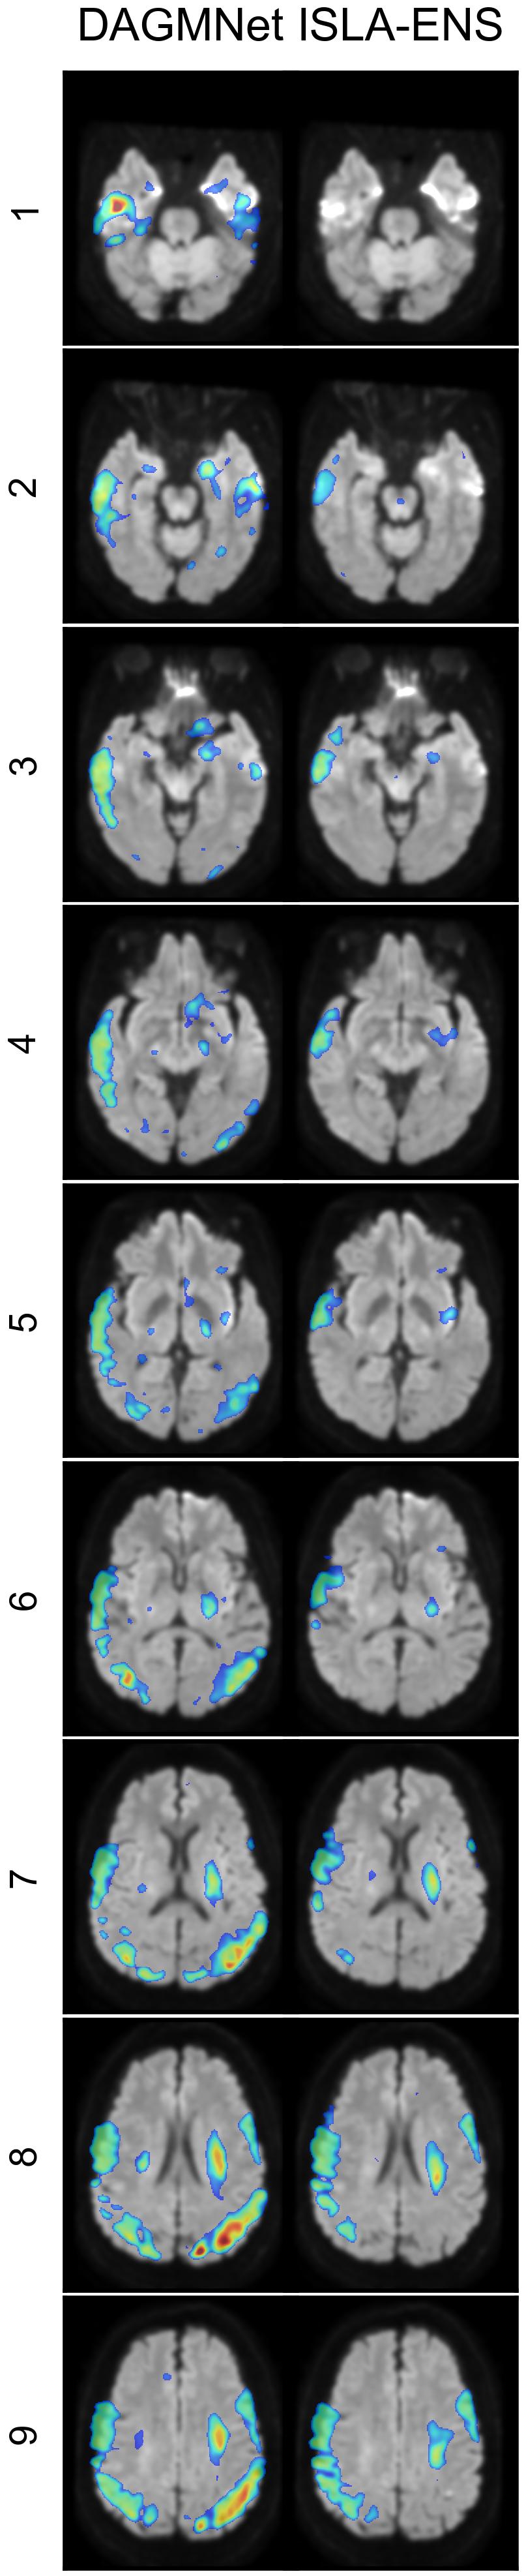

Figure 4 shows representative examples of segmentations from the test set with DAGMNet and ISLA-ENS, the best SOTA and ISLA models according to the test set case-level ranking (Table 5).

In cases 1 and 2 of Figure 4(a), both models successfully detected the lesions; however, DAGMNet slightly underestimated the lesion extent in case 1. In case 3, a corticospinal tract anisotropy artifact resulted in FPs for DAGMNet.

Cases 1 and 3 of Figure 4(b) further illustrate underestimation of lesion extent by DAGMNet, whereas ISLA-ENS produced segmentations closely matching the manual annotations. In case 2, both models generated FPs due to magnetic-susceptibility artifacts near the nasal region.

In Figure 4(c), case 1 shows accurate delineation of the lesion by both models, with no FPs induced by the inhomogeneity artifact. Case 2 demonstrates a missed small cerebellar lesion by ISLA-ENS. In case 3, both models correctly localized the lesion, but DAGMNet again produced FPs caused by magnetic-susceptibility artifacts around the nose.